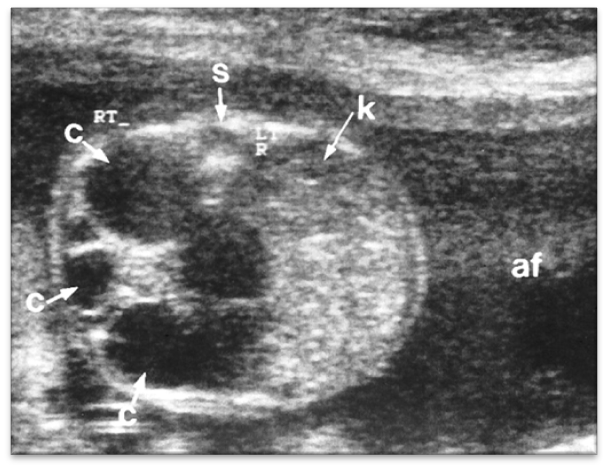

multicystic kidney disease